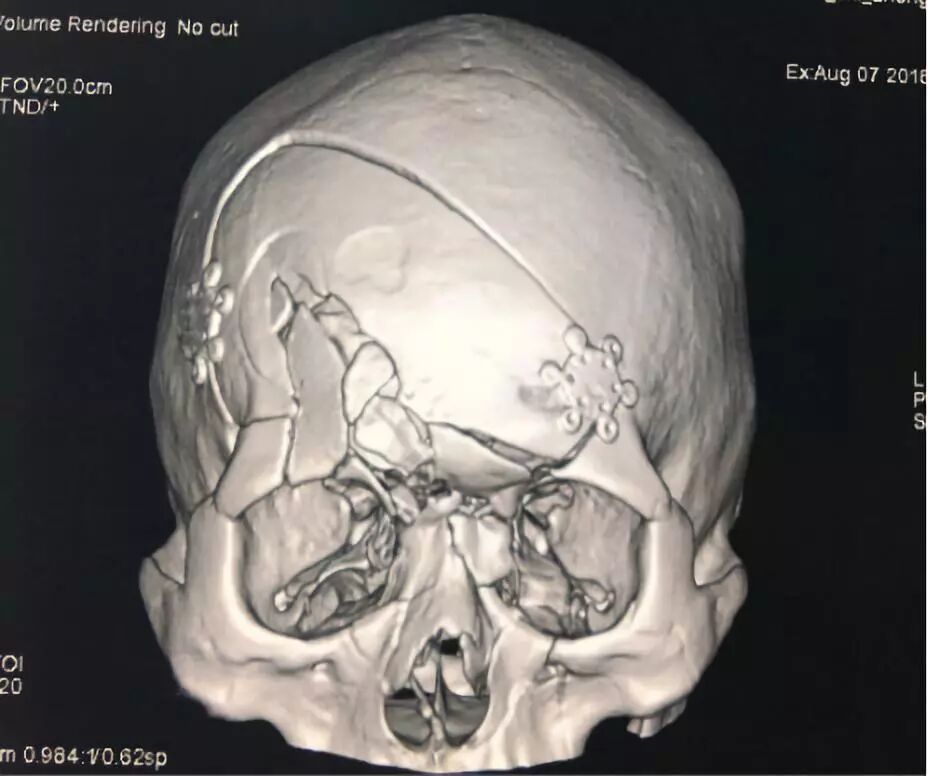

术后CT

![]()

术后一月恢复顺利,无发热脑脊液漏,四肢肌力5级。